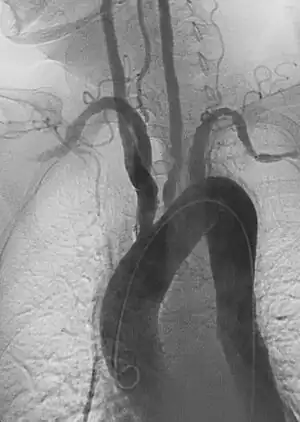

Aneurysm refers to pathologic dilation of an artery to greater than 1.5 times its normal size. True vascular aneurysms are due to degenerative processes in the wall of the artery. Aneurysms can be solitary or multiple and are sometimes found in association with various clinical syndromes, including forms of vasculitis or connective tissue diseases. Aneurysms are typically classified by major shapes, either fusiform (tubular) or saccular (eccentric). Ectasia is another broad term for an enlarged vessel, but is not necessarily pathological. Rupture is a dreaded complication of aneurysms that can lead to extensive, difficult to control bleeding. Aneurysms can also clot, or thrombose, and rapidly occlude the involved vessel, leading to acute distal ischemia.

1. Aortic aneurysms include thoracic, abdominal and thoracoabdominal aneurysms. Treatment strategies are customized depending on the location, size, rate of growth and extent of the aneurysm as well as the medical comorbidities of the patient. For example, an intact, small but slowly growing aneurysm may be safely monitored with serial imaging for months or years before elective repair is considered. Elective endovascular aortic grafting is now routinely attempted when possible. Endovascular aortic repair (EVAR) refers to treatment of an abdominal aortic aneurysm, while thoracic endovascular aortic repair (TEVAR) is performed on the thoracic aorta. A ruptured aneurysm may be taken emergently for open, endovascular or combination repair.

A variety of endovascular grafts are available, and each has advantages and disadvantages depending on the characteristics of the aneurysm and patient.[90]